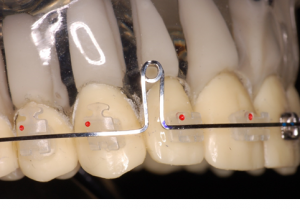

De modo geral, as descompensações são realizadas às custas de extrações e projeções dentárias nos arcos antagônicos. Nas Classes III, as extrações recaem sobre os pré-molares superiores e na projeção dos incisivos inferiores. Nas Classes II, a situação inversa irá ocorrer, com a extração dos pré-molares inferiores e a vestibularização dos incisivos superiores. Diante desse quadro, torna-se primordial explicar aos pacientes e seus responsáveis que durante esse processo as discrepâncias esqueléticas se tornarão mais evidentes, o que irá piorar temporariamente o aspecto facial do paciente. O reequilíbrio da face só acontecerá após a cirurgia ortognática.

O primeiro passo, ao se planejar esses casos, consiste em reposicionar os incisivos numa angulação mais próxima do ideal possível em relação às suas bases ósseas. Dessa forma, podemos levar em consideração as avaliações cefalométricas do longo-eixo dos incisivos superiores com o plano palatino (1.pp) e dos inferiores com o plano mandibular (IMPA). Embora outras medidas cefalométricas possam ser utilizadas nessa avaliação, considerar a boa relação dente-osso nos parece bem mais óbvio nesse momento e quantifica o movimento necessário para a sua descompensação.